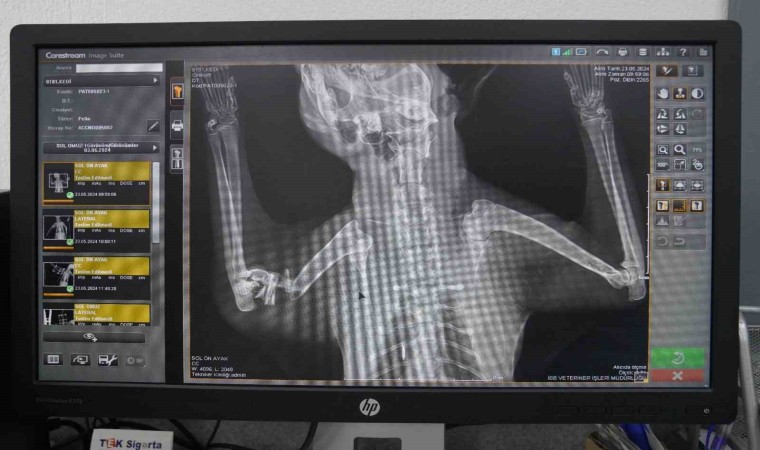

Ameliyat hakkında bilgi veren Veteriner Hekim Mehmet Uysal, ortopedi biriminde kedinin bacağının durumunu tespit ettiklerini belirterek, “Bacağının ciddi şekilde parçalandığını gördük. Burada sağlığına kavuşması için hemen gerekli cerrahi tedaviyi uyguladık. Bacağında parçalanan kemikleri özel bir aparatla sabitledik. Güvenli bir yöntem olduğu için bunu tercih ettik. Kedimiz 25 gündür bu şekilde tedavi altında. Bir süre sonra bu taktığımız aparatın kırıklar üzerindeki etkisine bakacağız. Bacak iyileşmiş olursa çıkaracağız. Şu anda sağlığı ile alakalı bir problemi yok. Keyfi yerinde. Bacağını nasıl kullanacağını öğreniyor diyebilirim” diye konuştu.

Bu yöntemin zorlu ve maliyetli olduğunu da aktaran Uysal, “Biz böyle bir tedavi uygulamamış olsaydık kedinin bacağını ampute etmek zorunda kalacaktık. Çünkü iyileşme ihtimali çok düşük bir kırık. Biz bu şekilde şans vermek istedik. O da bizim tedavimize çok güzel bir şekilde cevap verdi. Muhtemelen de iyileşip buradan gidecek. En büyük temennimiz kendisine yuvasının kapısını açacak iyi yürekli bir aileyle birlikte buradan ayrılması” cümlelerine yer verdi.